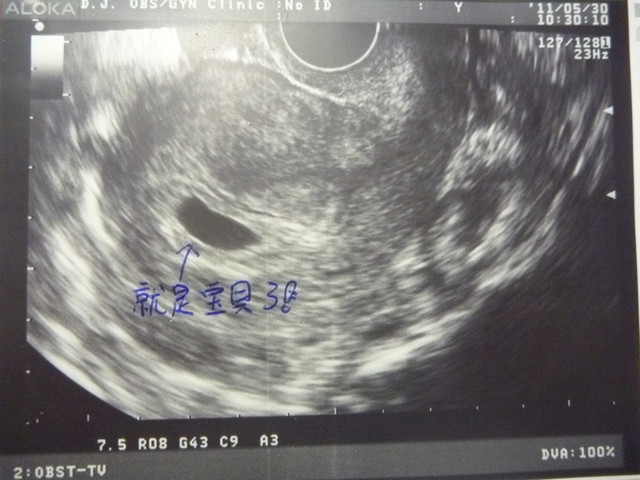

這次再見淘氣二寶~

竟比上次週數又大更多~

今日估約四週多~

所以預產期先押在2012/01/27~

不過這次尚未看見卵黃囊~

所以林醫師要我一週追蹤一次會比較安全!!

目前正常長大唷!!

初期不穩定~要持續追蹤~